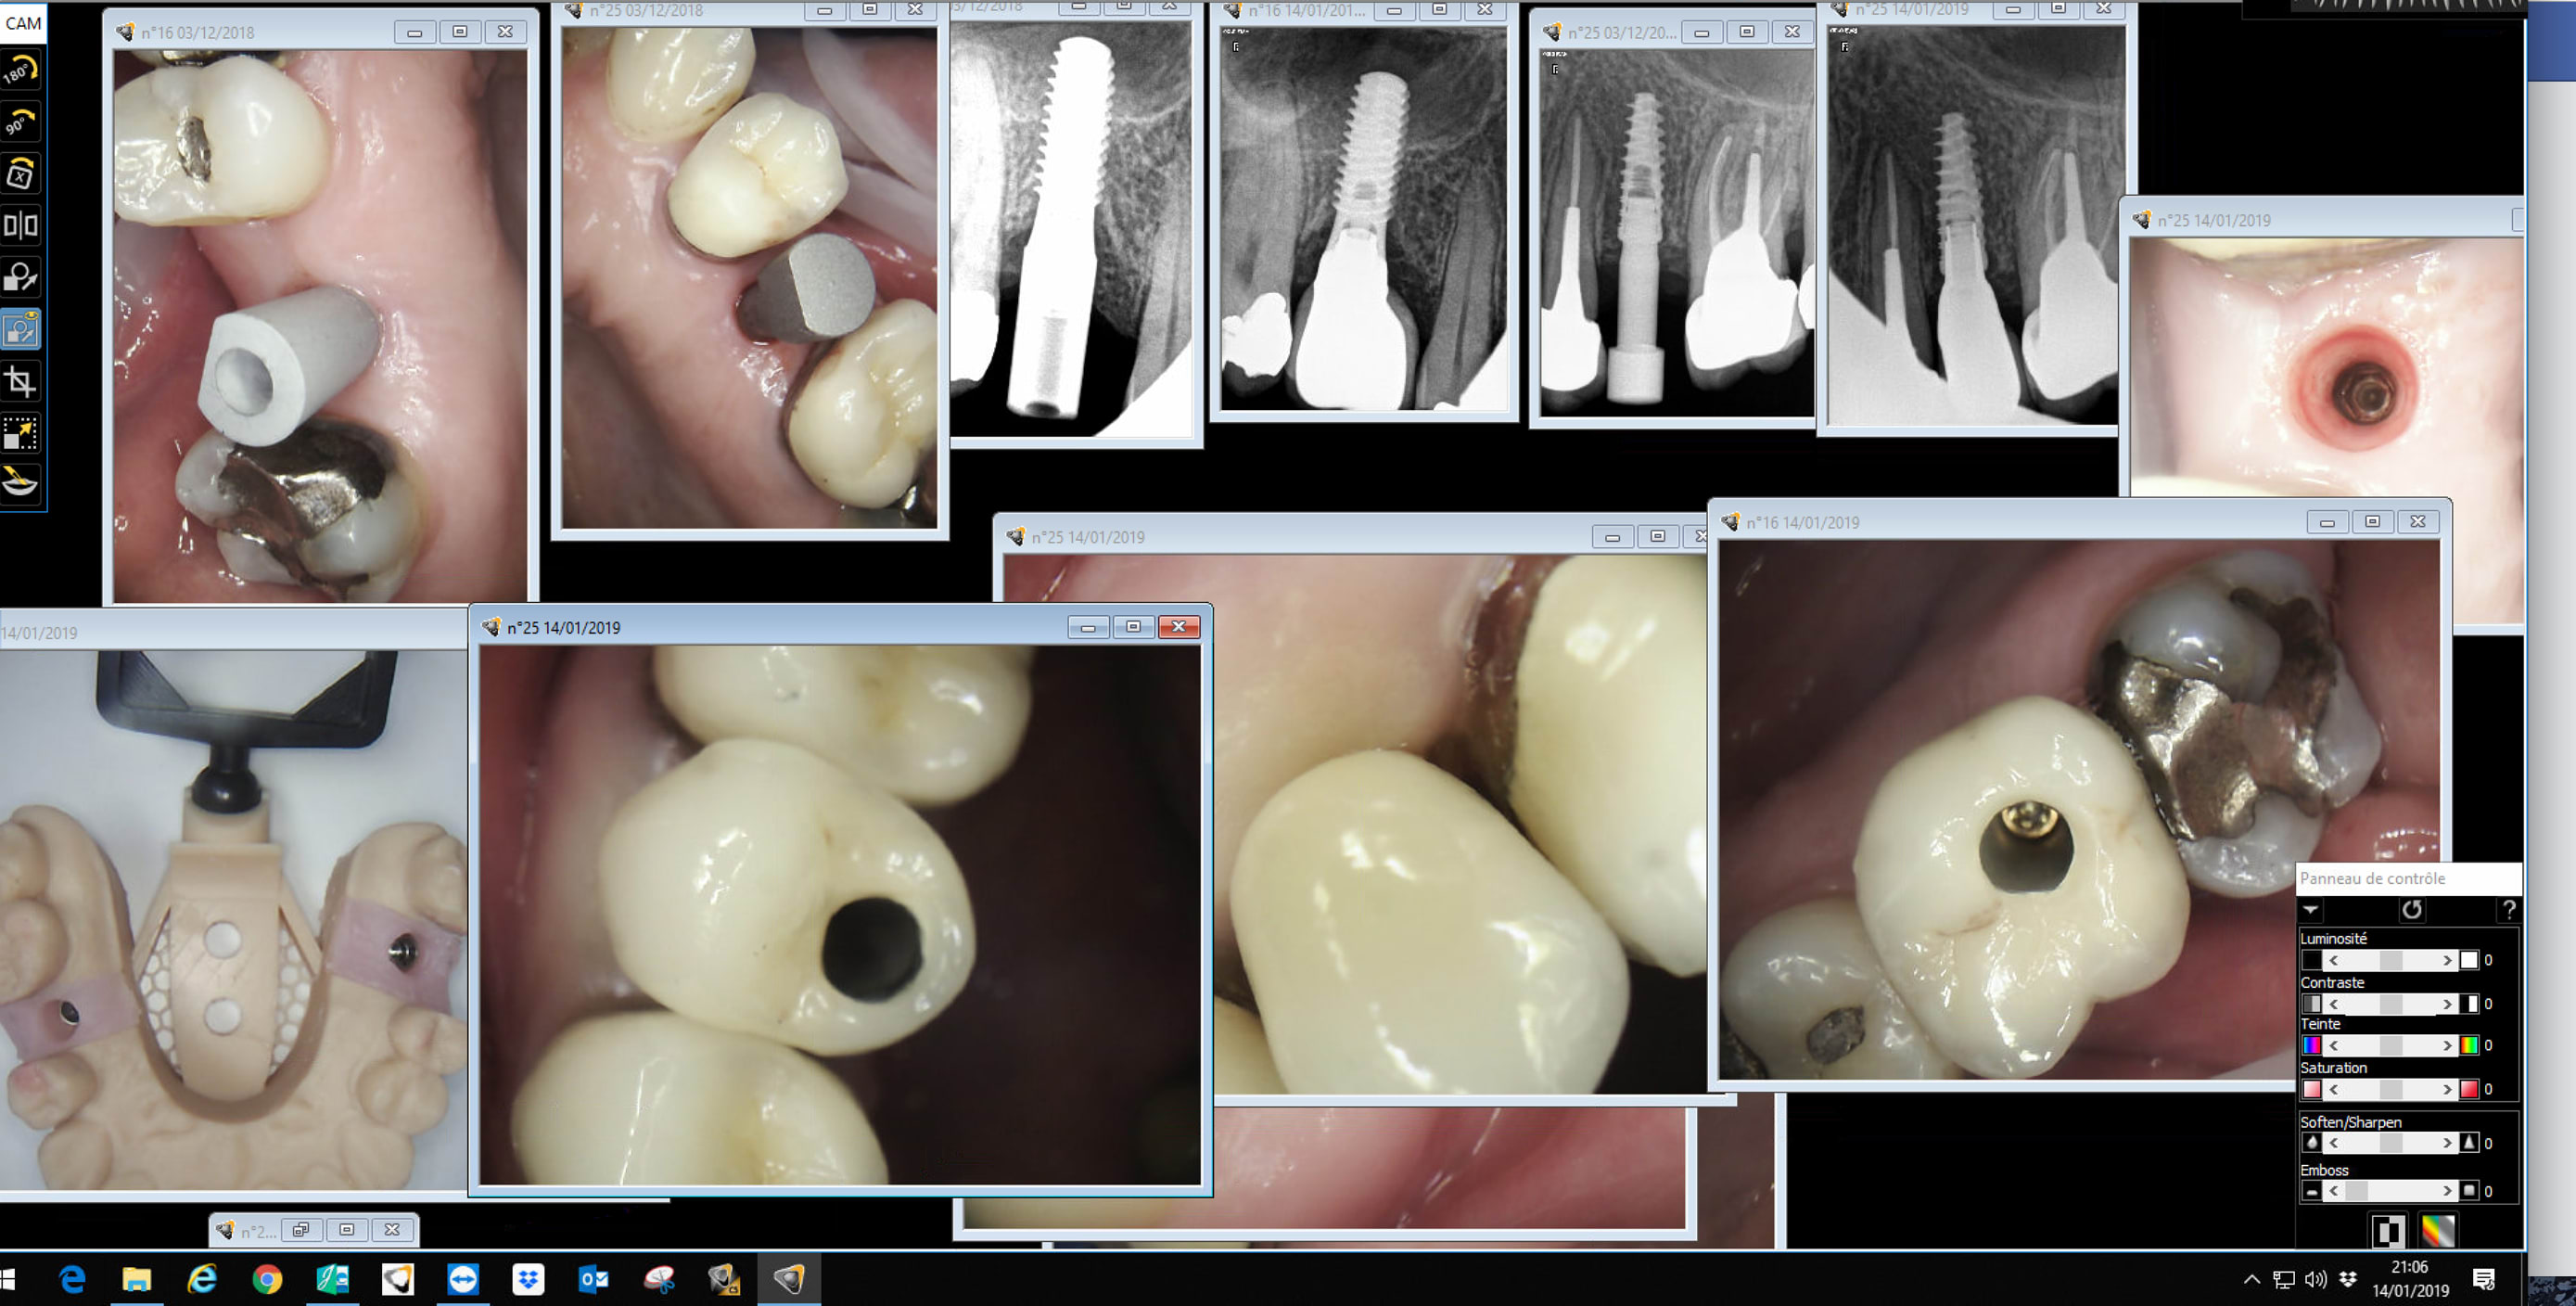

La j'ai un cas d'implanto 25 26 27 que je vais pouvoir faire avec la cam cette semaine.

A ce propos j'aurais besoin de conseils au niveau des scanbodies a utiliser pour des implants nobel...

Faut que je prenne ceux la ?? y'a une alternative ??

Si j'ai bien compris il faut également utiliser le tourne-vis spécifique...